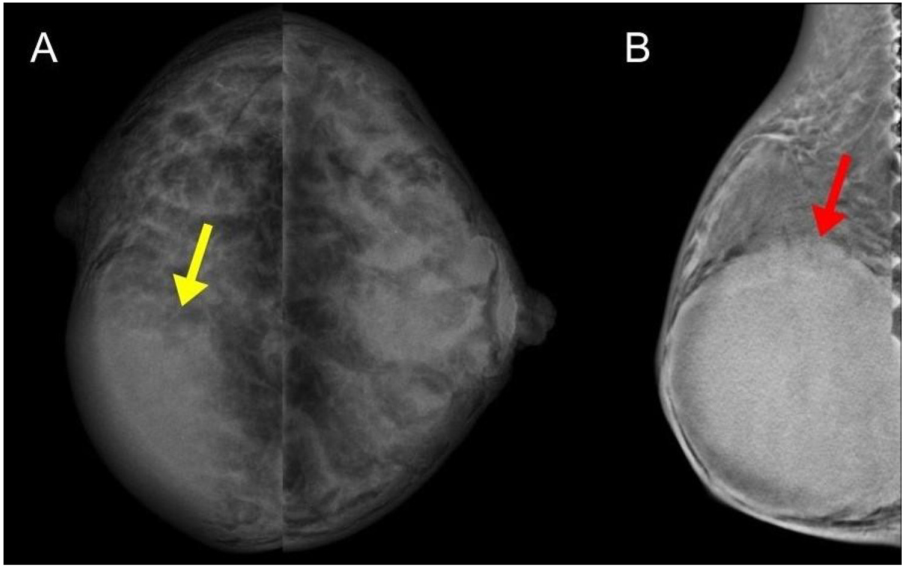

乳腺钼靶(图 2A、2B):右乳内下象限见高密度、边界规整结节,断层合成技术显示边缘更清晰。

图 2 (A)双侧数字化乳腺钼靶(头尾位):右乳内侧象限可见高密度结节,边界规整(黄色箭头);(B)右乳单侧断层合成成像:更清晰显示结节边界规整特征(红色箭头)。